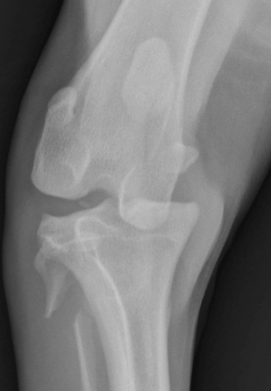

Once the patient is stable, X-rays are essential. While most dislocations are easy to see on radiographs, isolated ligament injuries may be missed.

In these cases, stress radiographs — taken while applying a controlled force to the joint — are often necessary to demonstrate instability.

Comparing images with the opposite, uninjured limb helps identify abnormalities and plan treatment. For more complex injuries, CT scans can provide